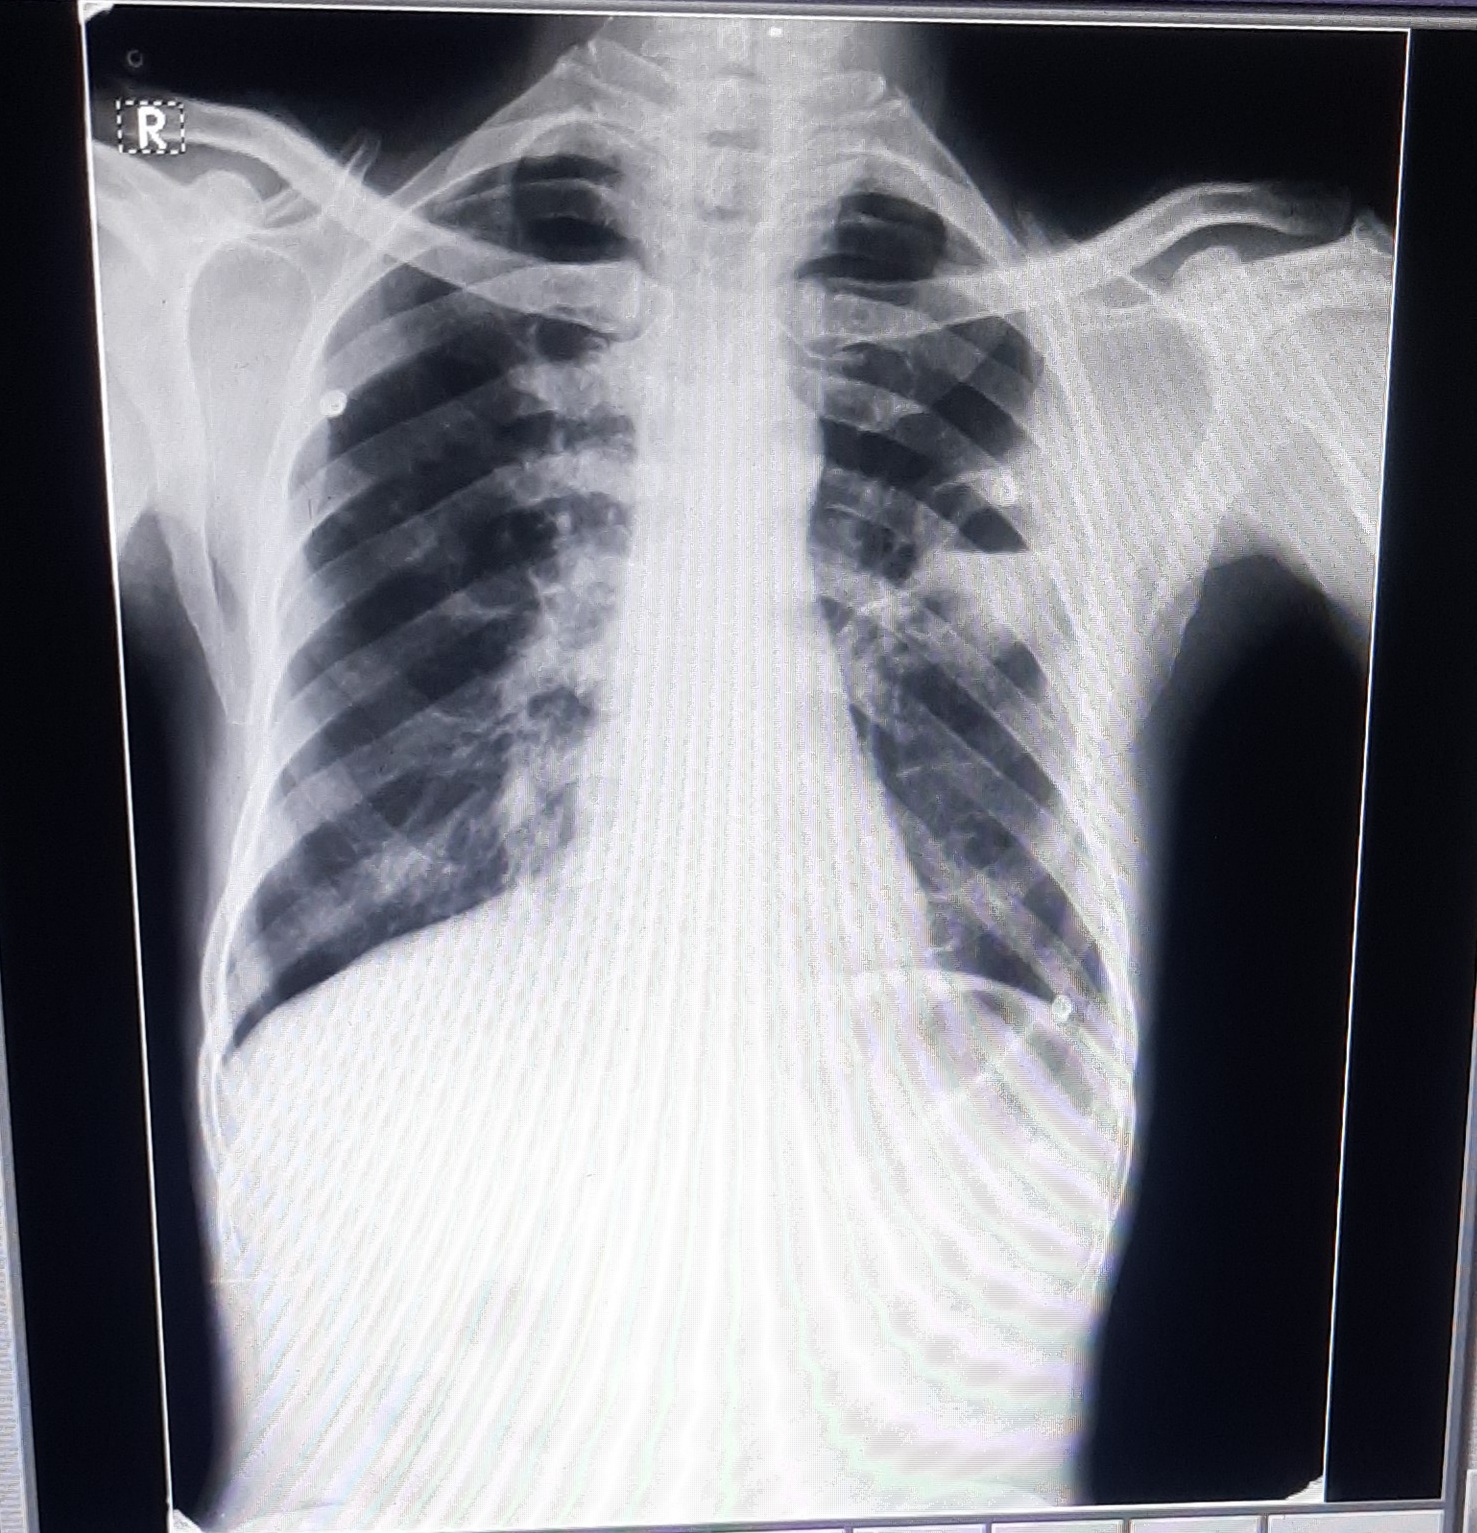

RS:BAE+,NVBS.